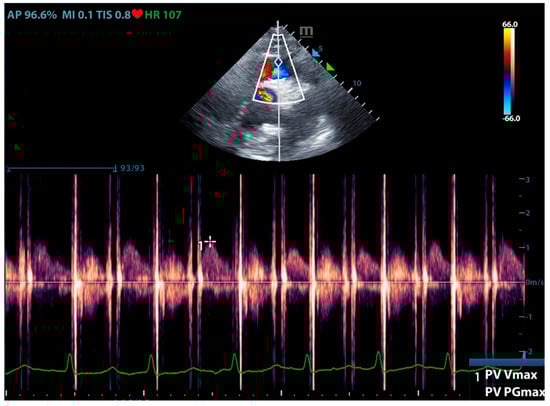

Physicians can assess pulmonary artery pressure quantitatively with point-of-care ultrasound. According to Bernoulli’s principle, the systolic pressure and diastolic pulmonary artery pressure can be estimated, respectively, by measuring the maximum regurgitation velocity of the tricuspid valve and the pulmonary valve. The maximum regurgitation velocity of the tricuspid valve (TVR Vmax) can be measured in the apical four-chamber view (Figure 6), and the maximum velocity of the pulmonary artery valve regurgitation (PVR Vmax) can be measured in the pulmonary artery long-axis view (Figure 7). Physicians can estimate pulmonary artery systolic pressure (PASP), diastolic pressure (PADP), and mean pulmonary artery pressure (mPAP) based on the ultrasound-measured TVR Vmax and PVR Vmax by the following formulas:

PASP = TVR Vmax2 + RAP(CVP)

PADP= PVR Vmax2 + RAP(CVP)

mPAP = 1/3 ∗ PASP + 2/3 ∗ PADP

Figure 7.

The ultrasound measurement of the maximum velocity of the pulmonary artery valve regurgitation.

This can not only be used for the diagnosis of pulmonary hypertension but also for continuous and dynamic evaluation of pulmonary artery pressure [26]. It should be noted that the use of tricuspid regurgitation velocity to estimate pulmonary artery pressure with ultrasound Doppler has limitations. When the patient has severe tricuspid valve disease or severe right heart dysfunction, using the maximum tricuspid regurgitation velocity may underestimate the pulmonary artery pressure. Therefore, the evaluation of pulmonary hypertension should be combined with other ultrasound signs of the right ventricle, pulmonary artery, inferior vena cava, and right atrium.